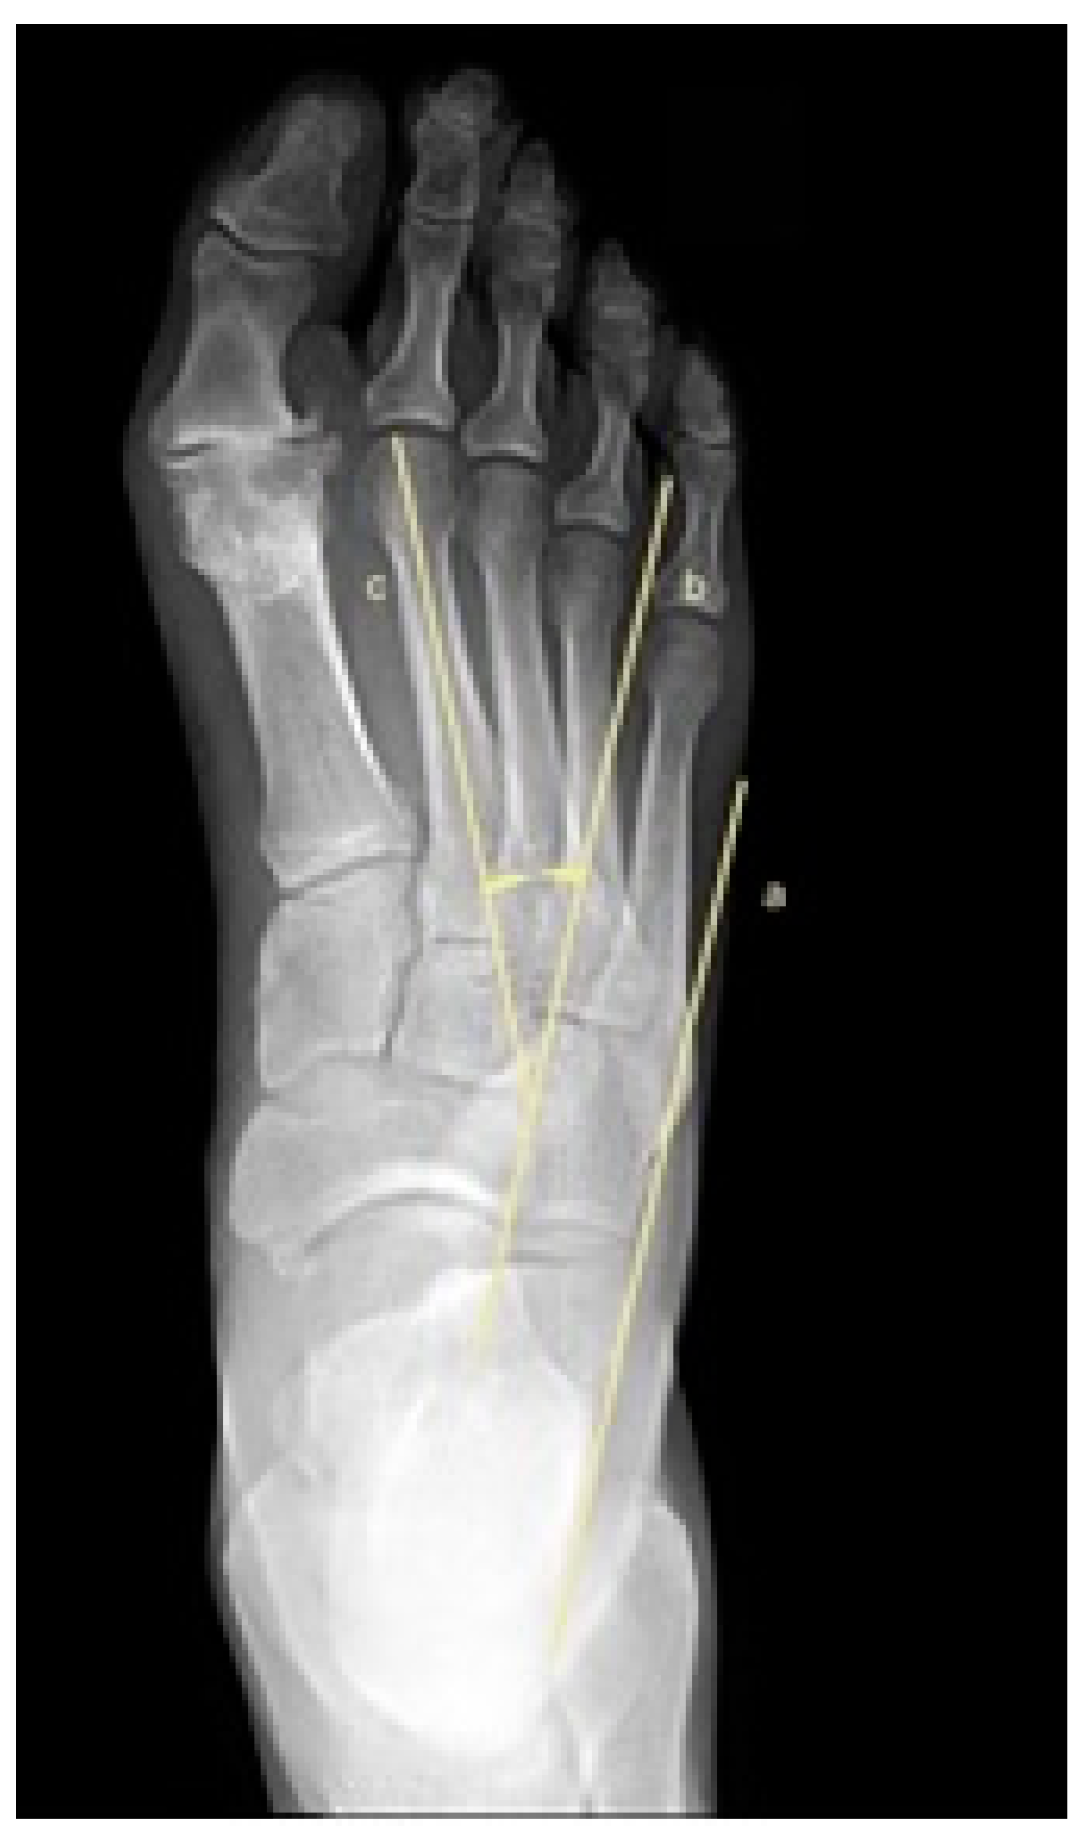

2.5. Metatarsus Adductus Measurements

- Kilmartin, T.E.; Flintham, C. Hallux valgus surgery: A simple method for evaluating the first-second intermetatarsal angle in the presence of metatarsus adductus. J. Foot Ankle Surg. 2003, 42, 165–166. [Google Scholar] [CrossRef]

- Dawoodi, A.I.S.; Perera, A. Radiological assessment of metatarsus adductus. Foot Ankle Surg. 2012, 18, 1–8. [Google Scholar] [CrossRef]